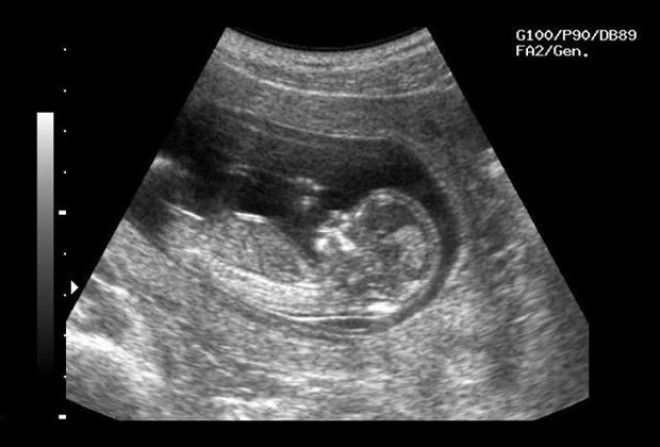

Ультразвук и соотношение полов

КОГДА: 1960 год — наши дни

ЧТО ИЗМЕНИЛОСЬ: мальчики стали рождаться чаще девочек

По статистике, женщин, которые на ранних этапах беременности вынашивают девочек, немного больше, чем тех, кто готовится родить мальчика. Но на более поздних этапах это соотношение меняется. Причина тому — технологии, а конкретно УЗИ.

С конца Первой мировой войны ультразвук применяли для того, чтобы подводные лодки могли ориентироваться в тёмной мутной воде. Через 30 лет обнаружили, что таким образом можно находить камни в жёлчном пузыре у собак, а ещё через 10 лет оказалось, что человеческий плод тоже можно исследовать с помощью ультразвука. Таким образом, люди научились по внешнему виду плода ещё в утробе матери определять его пол.

Реклама

Мара Хвистендаль, автор книги «Неестественный отбор»,утверждает, что мир за последние несколько десятилетий недосчитался 160 миллионов девочек. Их потенциальные матери, придя на УЗИ и узнав пол ребёнка, предпочли сделать аборт. Особенно сильно пострадала Азия, где мужчины занимают гораздо более высокое положение в обществе, чем женщины, а жизнь и благополучие последних не очень-то ценятся. Например, в Китае в 2010 году мальчиков было 54,14 %, девочек — 45,86 % от общего числа детей.